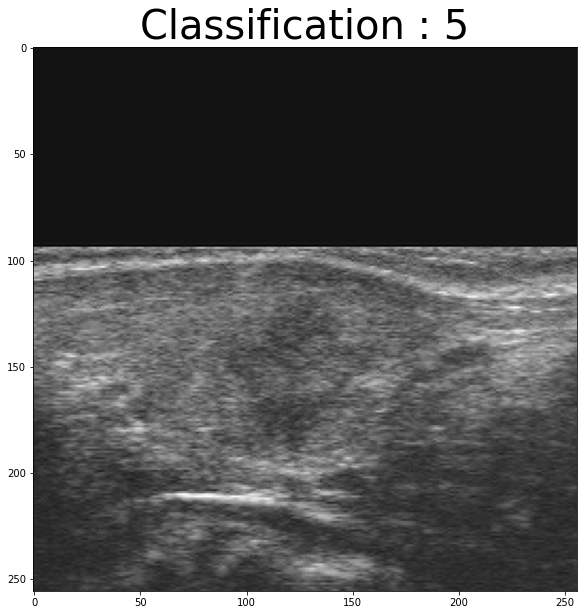

x=normalize(data)Let’s see , random examples from X :

import random

random_number=random. randint(0,len(df["Tirads"]))

plt.figure(figsize = (20,10))

tit="Classification : "+np.str(df["Tirads"][random_number])

plt.title(tit,fontsize = 40)

plt.imshow(x[random_number,:,:,0],cmap="gray")